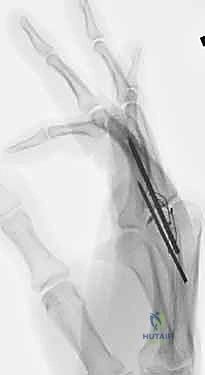

- Kirschner Wire (K-wire) Fixation:

- Advantages: Simplicity of technique, ready availability, low-cost implants. Historically, fusion rates up to 99% have been reported.

- Disadvantages: Less rigid fixation, often requiring additional external immobilization (splint/cast) which can lead to stiffness in surrounding joints. Higher risk of infection (superficial pin site, deep wound, osteomyelitis). Potential for pin migration. Minimal compression across the fusion site, which is biomechanically less favorable.

- Tension Band Fixation: This is a biomechanically superior method, often considered the gold standard for small joint arthrodesis.

- Mechanism: It combines parallel Kirschner wires for rotational control with interosseous wiring for compression. The genius of this